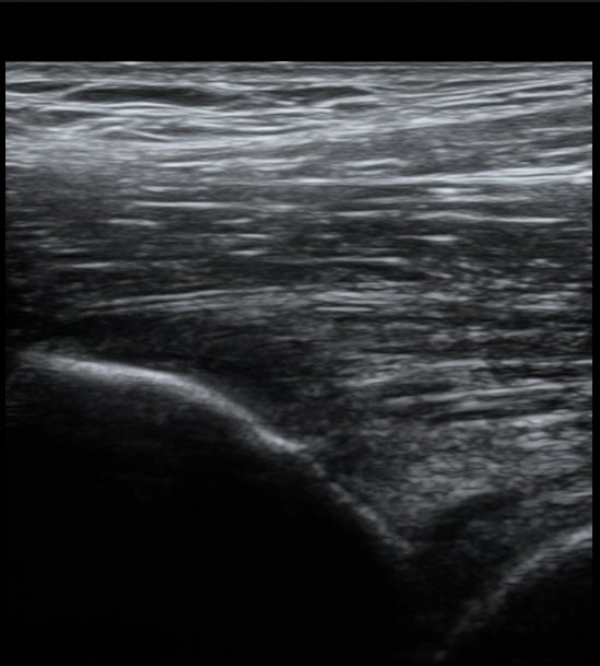

ŽÃËÀÚ¸¦ Á¶±Ý ³»ÃøÀ¸·Î À̵¿ÇÏ´Ï ÈûÁÙÀÇ °í¿¡ÄÚ°¡ ¼Ò½ÇµÇ¾î º¸ÀδÙ(»çÁø 2, 3)

ÀÌ º´Àû º¯È­´Â Á¤»óÃø(»çÁø 6, 7)°ú ºñ±³ÇÏ¸é ¶Ñ·ÈÇÏ´Ù.)

´ëÅðÁ÷±Ù ÈûÁ٠Ⱦ´Ü¸é °Ë»ç¿¡¼­µµ ÈûÁÙÀÇ Àú¿¡ÄÚ º¯È­¸¦ º¸À̰í(»çÁø 4, 5) ÀÌ º´Àû º¯È­µµ

°ÇÃø(»çÁø 6, 7)°ú ºñ±³ÇÏ¸é ½±°Ô ÆÇ´ÜµÈ´Ù.